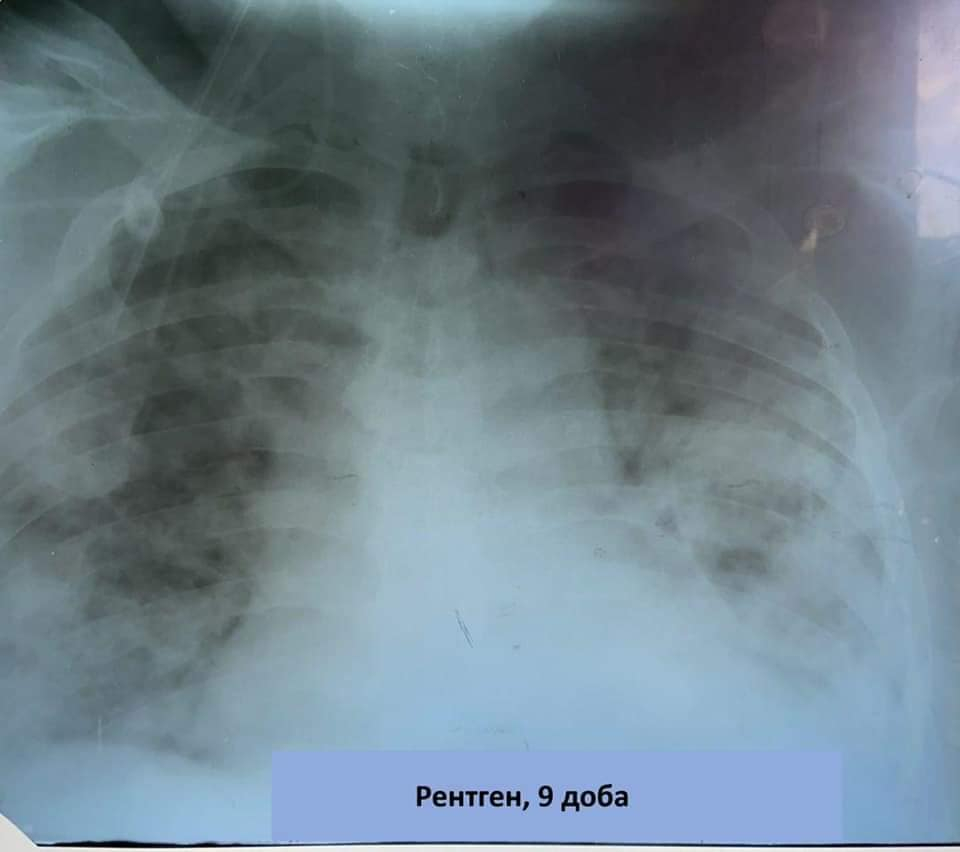

69-річний прикарпатець поступив в Івано-Франківську обласну клінічну лікарню на другий тиждень захворювання із дихальною недостатністю і гарячкою.

Стан пацієнта ускладнювали ожиріння ІІІ ст. (110 кг), єдина нирка та гіпертонічна хвороба ІІ ст.

"Індекс оксигенації 75 ммHg . Шанси були мінімальні. 22 доби штучної вентиляції легень, комбінована важка терапія. Застосовано і наш протокол. І вдалося. Чоловік повернувся до життя. Зараз самостійно дихає, періодично потребує О2 через носові канюлі. Велика щира вдячність усім медикам, а зокрема, Франківщини, які самовіддано і професійно рятують хворих. Особлива повага і гордість за команду анестезіологів на чолі з Ігорем Пуликом-обласним анестезіологом. Це надважлива і дуже тиха скромна перемога медиків і пацієнта", - розповідає посадовець.